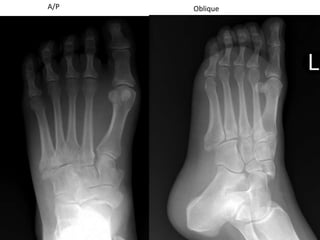

A/POblique

Navicular fracture (blue arrows) with cuneiform fracture (red arrows).  Navicularfxs have high incidence of avascular necrosis!  Need ORIF!!!